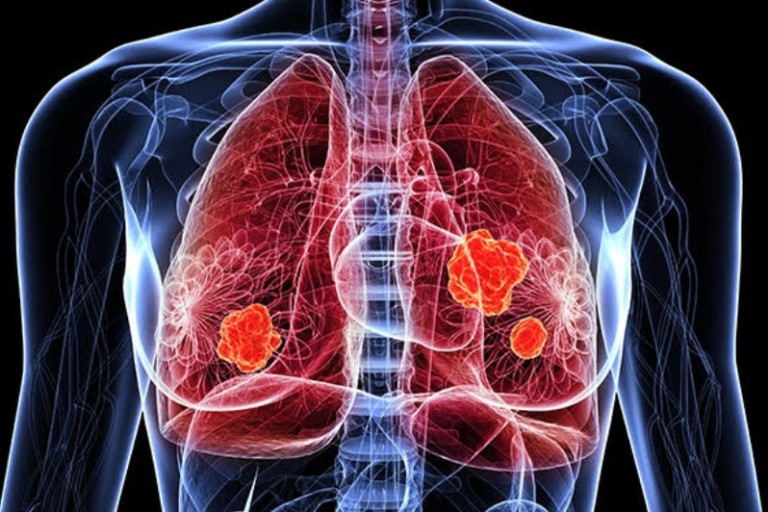

오늘은 우리 몸의 호흡을 책임지는 폐에 대해 이야기하려 합니다. 특히, 폐에 발생하는 악성 종양인 폐암의 초기 증상에 대해 자세히 알아보려 합니다.

폐암 초기에는 특별한 증상이 없는 경우가 많지만, 암이 진행되면서 다양한 신호를 보낼 수 있습니다. 다음은 폐암 환자들이 흔히 경험하는 10가지 주요 초기 증상입니다.

오늘 함께 알아본 폐암 초기 증상들이 여러분의 건강 관리에 큰 도움이 되었으면 합니다. 폐암은 조기에 발견하면 완치율이 높은 암이므로, 자신의 몸에 나타나는 작은 신호에도 귀 기울이는 습관을 들이는 것이 중요합니다. 오늘 알려드린 내용을 바탕으로 자신의 건강을 체크하고, 궁금한 점이 있다면 언제든지 전문 의료진과 상담하는 것을 잊지 마세요. 우리 모두 건강한 삶을 위해 노력해요!